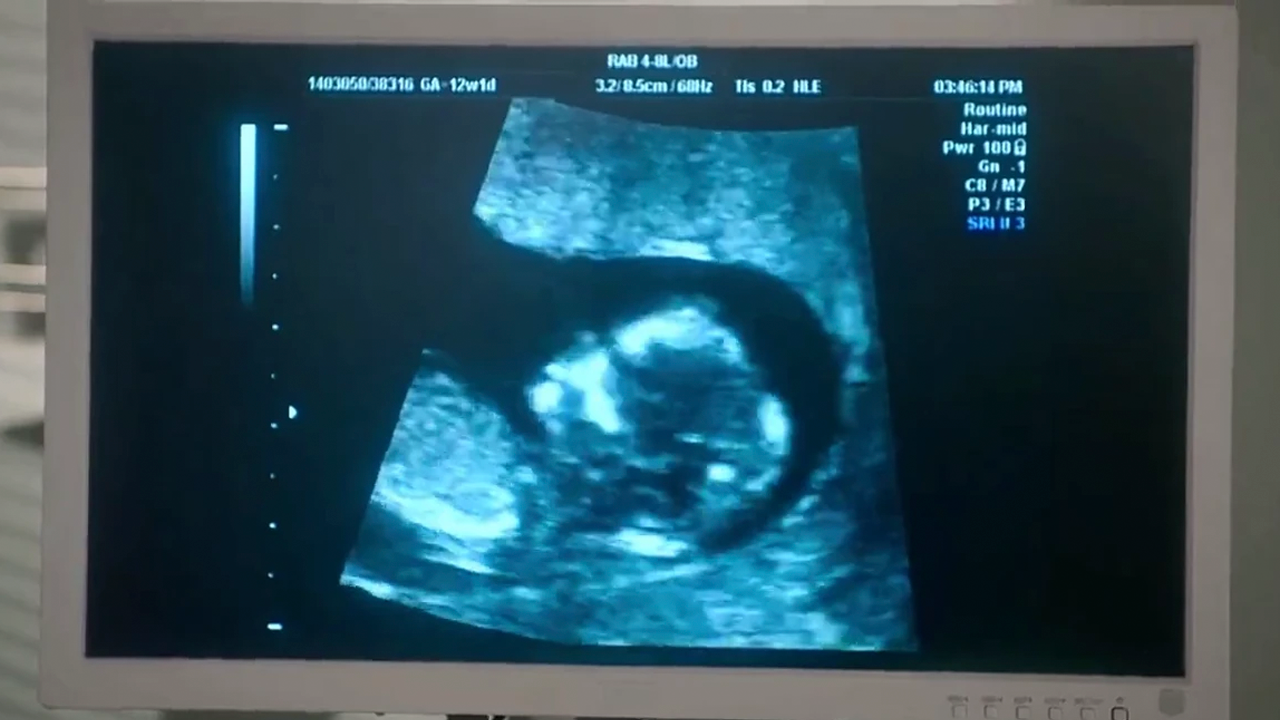

Uno de los aspectos más emocionantes de la temporada seis es el bebé que tendrán Johnny Lawrence y Carmen Diaz. En la quinta entrega, Carmen le dice a Johnny que se ha sentido mal y que su período se ha retrasado unos días. Teniendo sospechas de que realmente está embarazada, ambos compran una prueba y confirman que su intuición es cierta. Poco a poco, el elenco se va enterando de la noticia, mostrando momentos muy tiernos como el primer ultrasonido.